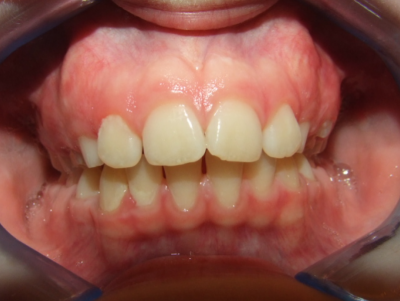

eindfoto

Beschrijving

Leeftijd bij aanvang: 10 jaar

Bonded Hyrax + volledig vast onderkaak

Volledig vast bovenkaak + expander

Wrap + c-c bar onderkaak

Leeftijd bij afname: 12 jaar